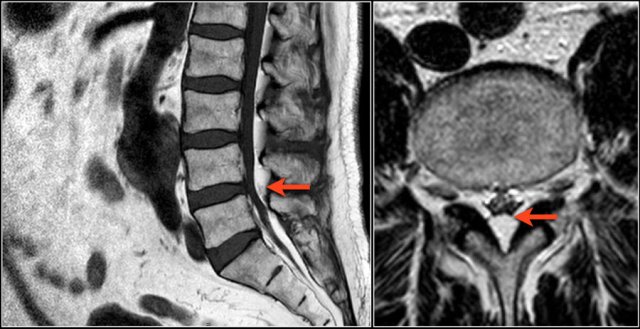

Here a disc herniation with upward migration.

By using the marker, you can correlate the abnormality on the T1W-image with the axial T2W-images.

On the T2W-image it is more obvious that this is a disc herniation.

The lower images are with the marker on.

you may have to enlarge the images to see it.

These foraminal disc herniations can be easily overlooked.

Notice how subtle the findings are on the axial T2W-images.

The herniated disc can be easily mistaken for the nerve root.

The sagittal T1W-image shows the upward migration of the disc.